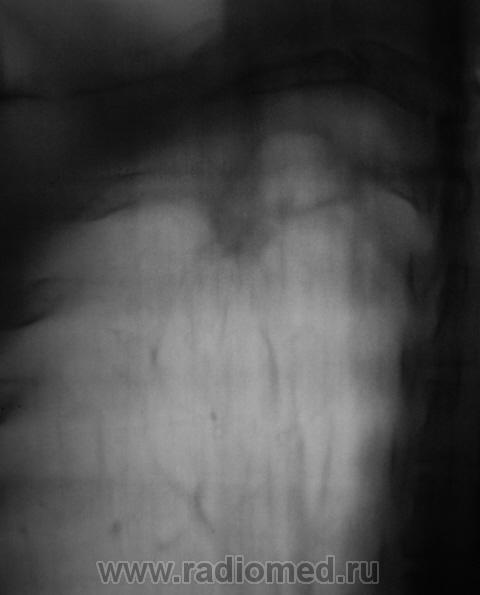

Пол пациента: Мужской пол Тип патологии: Инфекция Область исследования: Грудная клетка и верхние дыхательные пути Методы исследования: Rg При расшифровке цифровых флюорограмм пациент "взят на контроль". Смутила правая верхушка. Произведено стандартное дообследование. Ваше мнение коллеги? Пнд, 19/10/2009 - 22:26 #1 Наталия Не на сайте Был на сайте: 8 лет 7 месяцев назад Зарегистрирован: 30.07.2008 - 13:24 Публикации: 538 Полость на правой верхушке. Втр, 20/10/2009 - 07:40 #2 OPEXOB Не на сайте Был на сайте: 9 лет 11 месяцев назад Зарегистрирован: 26.07.2008 - 10:02 Публикации: 280 Ничего особенного. Повышенная пневмотизация и только. А томография 1 ребра хорошая. Втр, 20/10/2009 - 19:52 #3 Катенёв Валенти... Не на сайте Был на сайте: 7 лет 2 недели назад Зарегистрирован: 22.03.2008 - 22:15 Публикации: 54876 А что по поводу "полостного образования" мкажите коллега? Втр, 20/10/2009 - 20:08 #4 serega Не на сайте Был на сайте: 12 лет 4 месяцев назад Зарегистрирован: 15.10.2009 - 18:10 Публикации: 99 Прилежащая легочная ткань интактна- признаков воспаления нет, стенки плотные, полость "пуста". Быть может процесс старенький? Втр, 20/10/2009 - 20:17 #5 Глазков Игорь А... Не на сайте Был на сайте: 9 месяцев 2 недели назад Зарегистрирован: 19.12.2008 - 20:41 Публикации: 1597 похожа на туберкулёзную каверну. Прийди к Себе

Полость на правой верхушке.

Прилежащая легочная ткань интактна- признаков воспаления нет, стенки плотные, полость "пуста". Быть может процесс старенький?

похожа на туберкулёзную каверну.